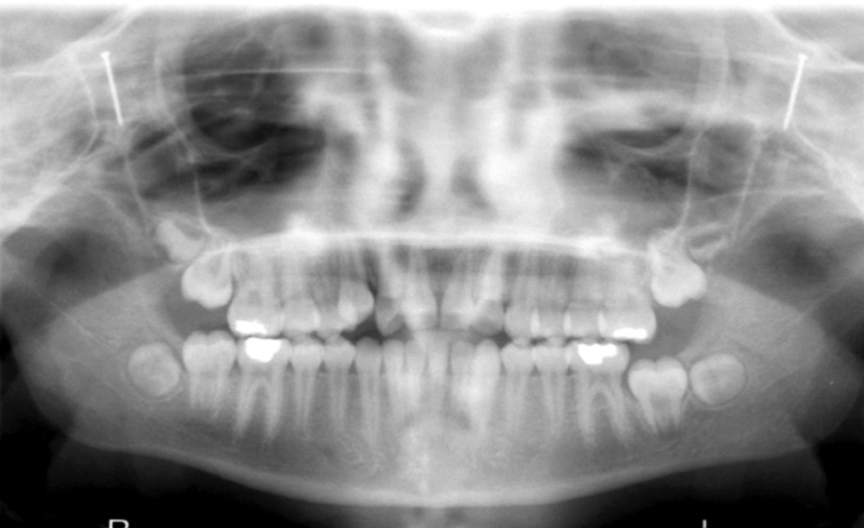

What errors can be seen in the following radiograph, what is the cause?

1. excessive curvature of the occlusal plane 2. roots of mandibular anterior teeth are blurred 3. rami/condyles are tipped inward 4. condyles are close to or cut off top of image 5. hyoid bone superimposed on mandible Cause: chin down